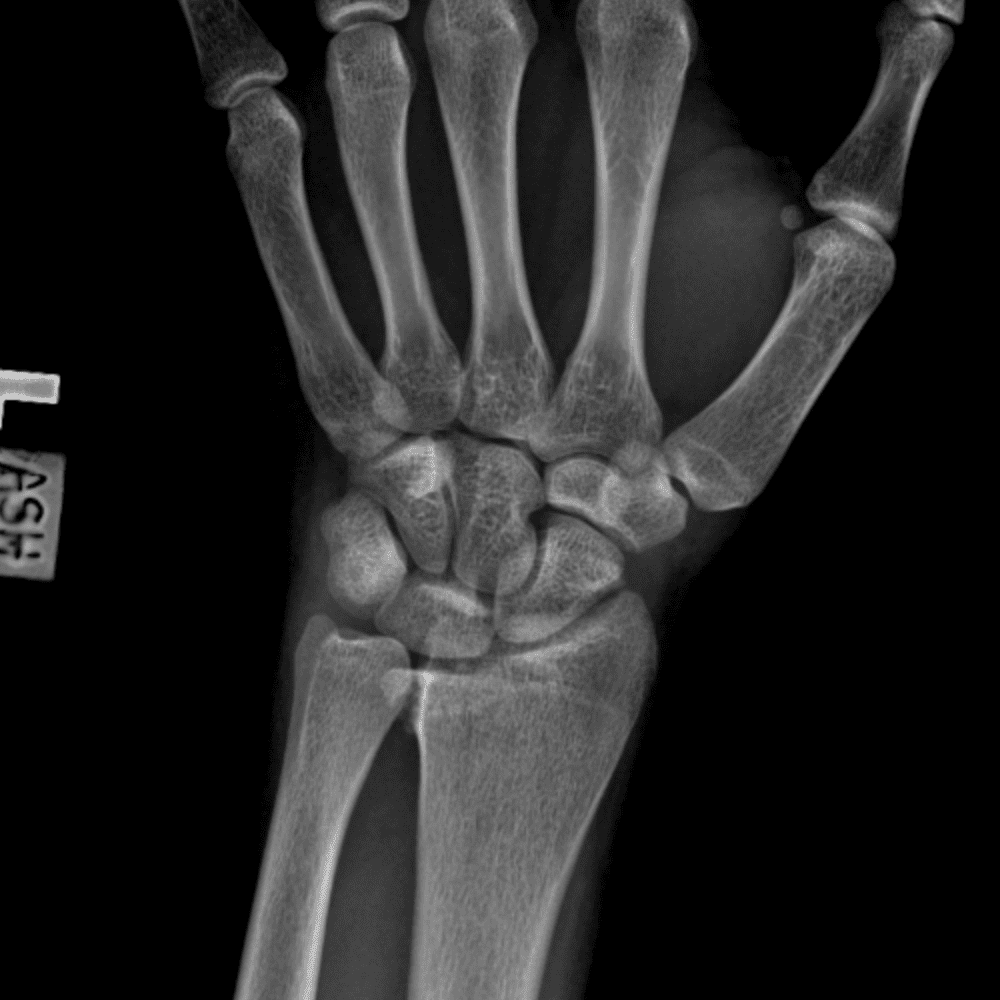

Simuliert den Dienst durch subtile oder schwierige Fälle und einige Normalbefunde.

30 Fälle